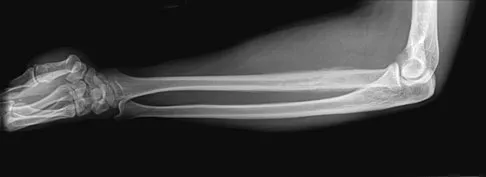

A 32-year-old woman sustained an injury to her left upper extremity in a motor vehicle accident. Examination reveals a 2-cm wound in the mid portion of the dorsal surface of the upper arm and deformities at the elbow and forearm; there are no other injuries. Her vital signs are stable, and she has a base deficit of minus 1 and a lactate level of less than 2. Radiographs are shown in Figures 9a and 9b. In addition to urgent debridement of the humeral shaft fracture, management should include

Explanation

With a severe injury to the upper extremity, the best opportunity for achieving a good functional result for a floating elbow is immediate debridement of the open fracture, followed by internal fixation of the fractures. The ability to do this depends on the patient's physiologic status. In this patient, the procedure is acceptable because she has normal vital signs and no chest or abdominal injuries, and normal physiologic parameters (base excess and lactate) show adequate peripheral perfusion. The surgical approaches will be determined by the associated injury patterns and open wounds. In this patient, the humerus was debrided and stabilized through a posterior approach as was the medial condyle fracture. The ulna was fixed through an extension of the posterior incision and the radius through a separate dorsal approach. Solomon HB, Zadnik M, Eglseder WA: A review of outcomes in 18 patients with floating elbow. J Orthop Trauma 2003;17:563-570.